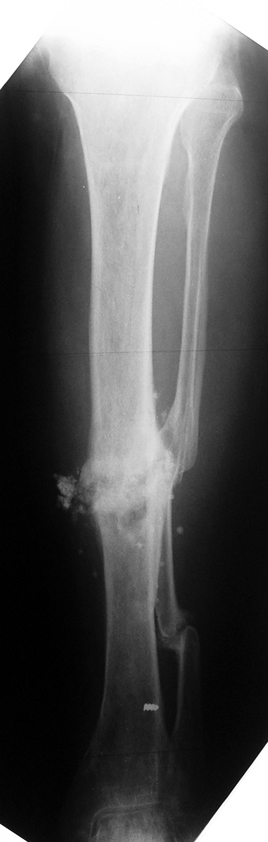

Tibia Osteomyelitis

Chronic Osteomyelitis

Chronic osteomyelitis leads to necrosis of bone and soft tissues. Dead bone is a nidus which hosts pathogenous microorganisms. Defence mechanisms of the host is usually not in optimum condition to deal with microorganisms. Antibiotics can’t reach the infection site because blood flow is disrupted. For these reasons, dead bone has to be completely removed by radical debridement.

Case 2